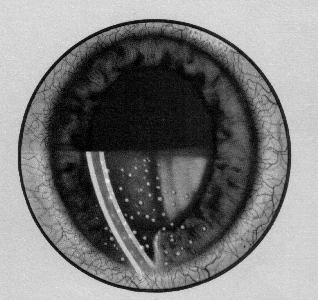

CHISTUL HIDATIC PULMONAR

CHISTUL HIDATIC PULMONAR Generalitati l Hidatidoza in general si hidatodoza pulmonara in particular reprezinta si astazi, ca si in trecut, o boala parazitara de larg interes medical atit pentru chirurgie cit siCiteste tot ... 2159 cuvinte

Dimensiune medie + cu poze |